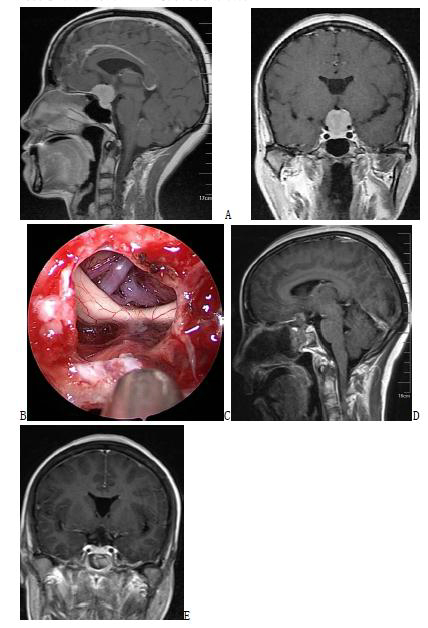

3. 颅咽管瘤

目前,绝大多数颅咽管瘤首选经鼻内镜手术切除。微创,反应轻微,对视力和内分泌损伤小,患者康复快。

图3. 六例实性侵袭第三脑室颅咽管瘤手术前、后的增强磁共振影像以及手术中截图,提示肿瘤全部切除,可以看到第三脑室后壁、室间孔和中脑导水管上口。